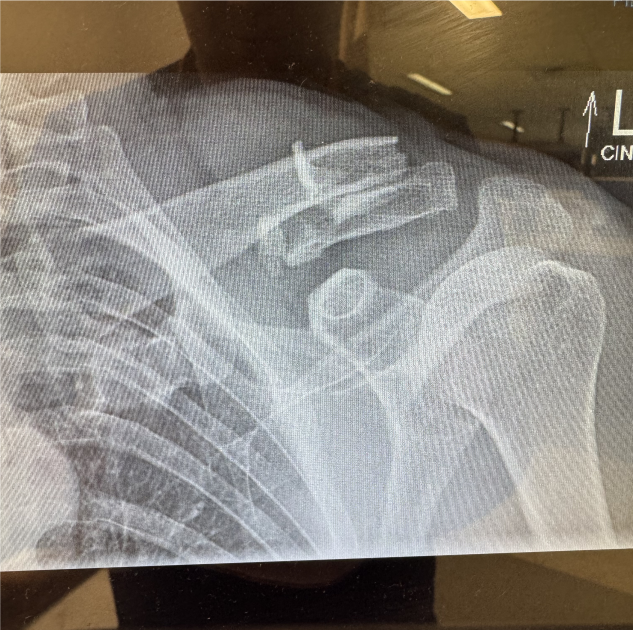

Here’s where the story gets wild — no blood. Not a scratch on him, though the x-rays later confirmed a broken collarbone and a few ribs that now double as percussion instruments. He’s currently at home, recovering like a champ and waiting for surgery, saying things like: